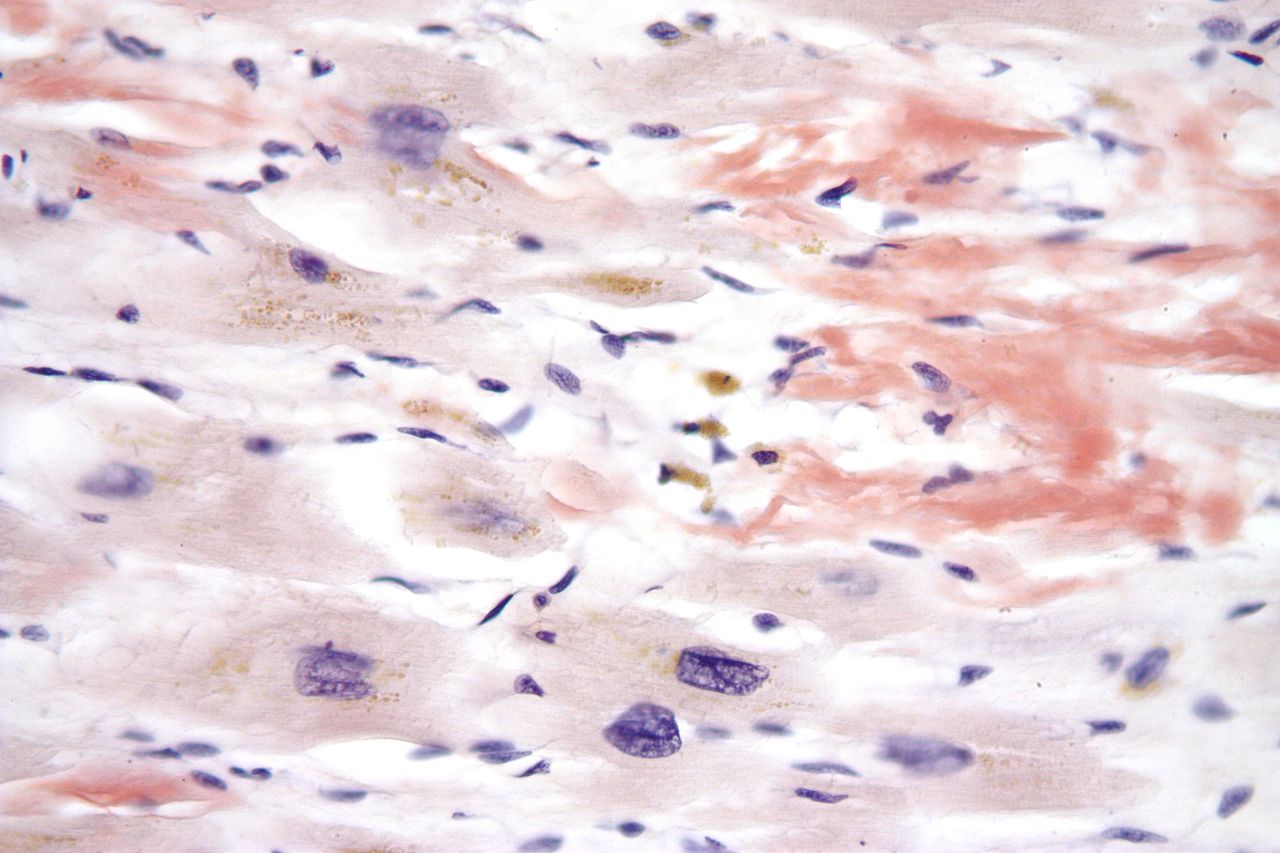

El miocardi o múscul cardíac (textus muscularis striatus cardiacus) és el teixit muscular del cor. És l’encarregat de bombar la sang pel sistema circulatori a través de contraccions. El miocardi conté una xarxa abundant de capil·lars indispensables per cobrir les seves necessitats energètiques.

El múscul cardíac generalment funciona involuntàriament i rítmicament, sense tenir estimulació nerviosa. És un múscul miogènic, és a dir, autoexcitable. La irrigació sanguínia del miocardi és portada a través de les artèries coronàries (vegeu la figura).

Les fibres de Purkinje (o teixit de Purkinje) formen part del múscul cardíac i es localitzen a les parets ventriculars, per sota de l’endocardi. Aquestes fibres són cèl·lules musculars miocardials especialitzades que condueixen l’impuls elèctric que ocasiona la contracció coordinada dels ventricles del cor. En aquest sentit, el miocardi porta a terme un control elèctric mitjançant dues ordres:

La miocarditis, per la seva banda, és la inflamació del múscul cardíac. Sovint és la causa d’una infecció viral. Altres causes inclouen infeccions bacterianes, certs medicaments, toxines i trastorns autoimmunitaris. Les conseqüències de la miocarditis són diverses. Pot causar una malaltia lleu -sense cap símptoma- que es resolgui per si mateixa, o pot causar mal de pit, insuficiència cardíaca o mort sobtada.